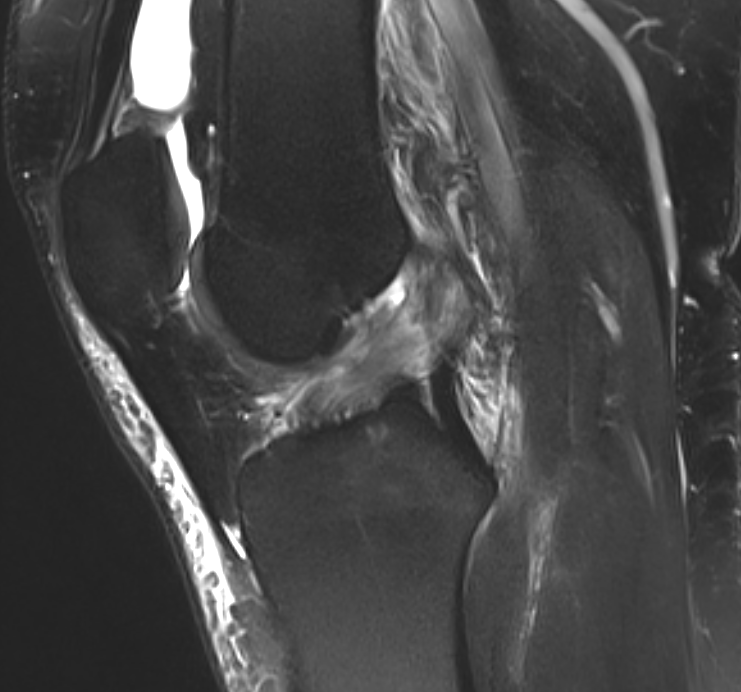

ACL tear